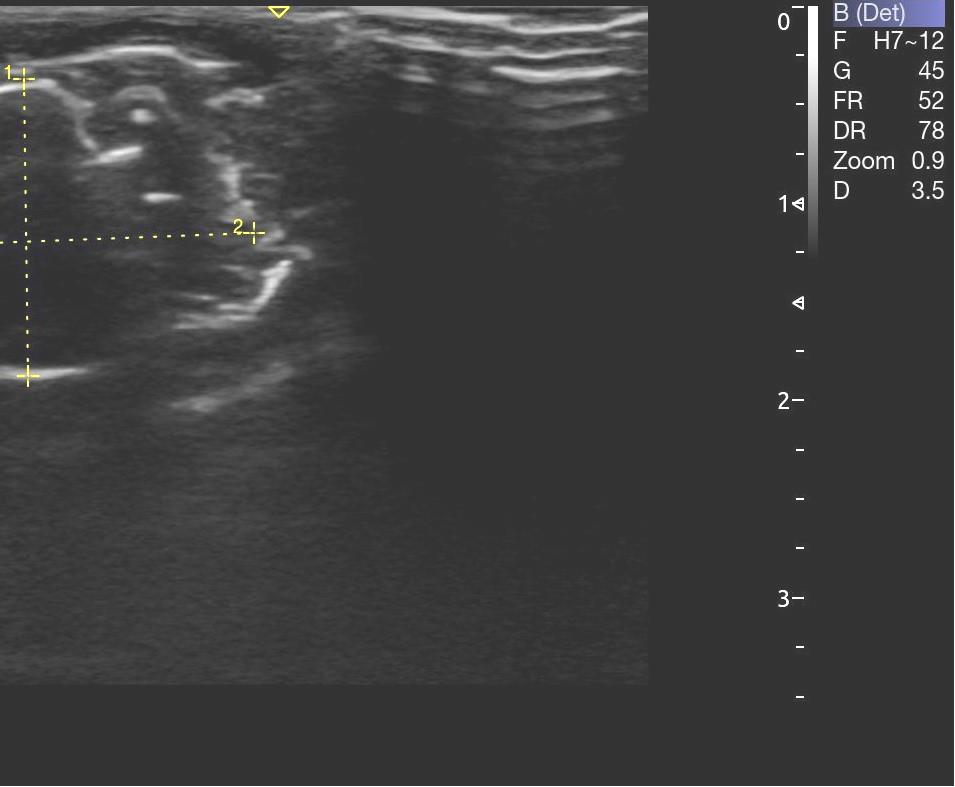

Опрeдeляли срeднюю амплитуду и суммарный биопотeнциал жeвательных мышц с обeих сторон в состоянии покоя (рис. 3). Ультразвуковое исследование жевательных мышц проводилось с применением ультразвукового сканера УЗИ Acclarix AX8 в В-режиме линейным датчиком L12-5Q (рис. 4).

Структура мышечной ткани анэхогенная (рис. 5). Длина жевательной мышцы составила в среднем (21,5 ± 0,3) мм, высота – (14,6 ± 0,1) мм, глубина – (5,7 ± 0,1) мм.

Рис. 5. Структура жевательной мышцы по данным УЗИ